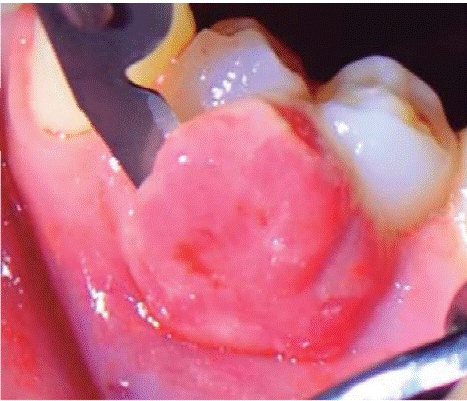

Al examen clínico se observa lesión gingival inflamatoria a nivel de piezas 3.4 y 3.5, de aproximadamente 15x9 mm, cubriendo la cara vestibular de la corona clínica, de consistencia firme, lobulada, textura rugosa y sangrante ante el estímulo (Figuras 1 y 2). A la evaluación periodontal no se detectaron bolsas periodontales, se observó presencia de placa, obteniéndose un índice de higiene oral (O'Leary) de 18.75%.

En la siguiente sesión se realizó la biopsia escisional de la lesión (Figura 4). En esta intervención se eliminó la lesión además de un margen de tejido sano llegando a remover el periostio adyacente. Se tomó la muestra para el examen histopatologico y fue transportado en formol al 10%. A continuación se realizó el recontorneado del tejido blando (gingivoplastia) (Figura 5) y se colocó un aposito de cemento periodontal. Se indicó analgésico por 48 horas y colutorios con clorhexidina al 0.12%, los cuales debieron ser suspendidos al quinto día debido a que la paciente presento lesiones del tipo ulcerativas a nivel de encía adherida por reacción alergica.

Tratamiento: primera sesión de instrucción de higiene oral seguido de biopsia excisional de lesión y gingivoplastia (Figuras 11 y 12).

Tratamiento: sesión de instrucción de higiene oral y biopsia excisional con gingivoplastia (Figura 23).